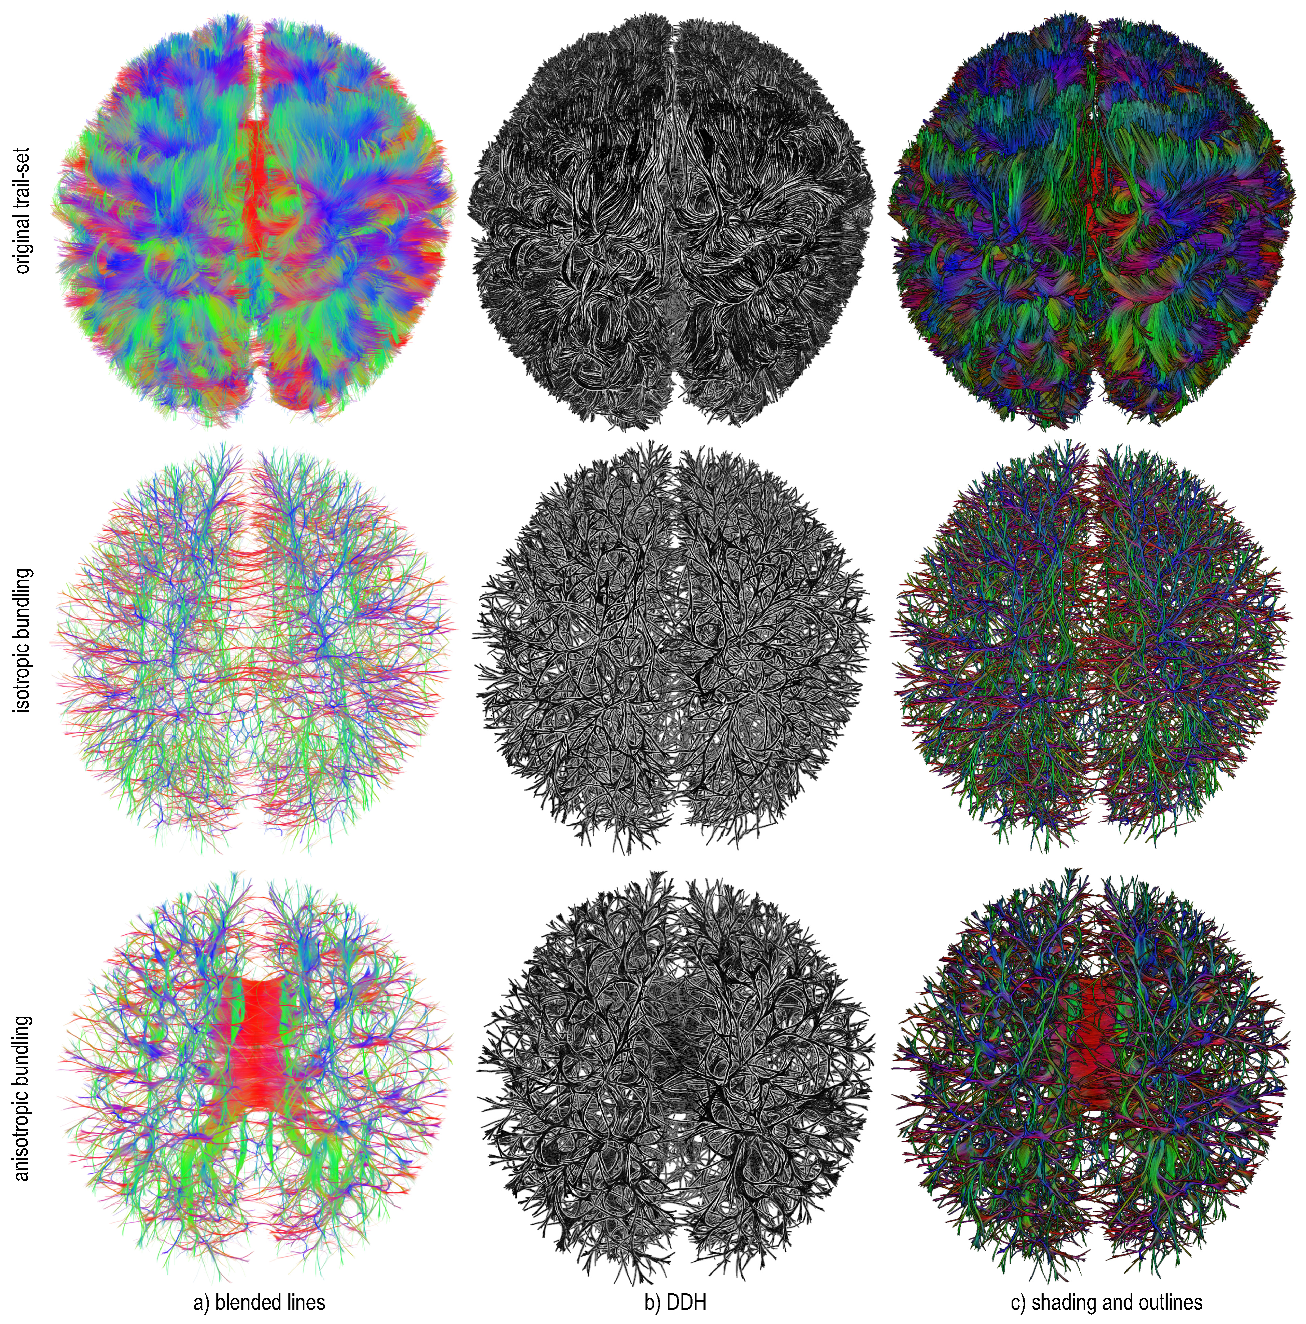

Figure 12 illustrates the above freedom of parameter choice. Here, we select a relatively small set of 65 K trails and render them, both unbundled and bundled, with four styles (blended lines, DDH, shading, and shading plus outlines), using isotropic bundling ( α 0 = 1 ). Trails are color-coded on direction. The blended lines style—which corresponds to the classical way DTI trails are rendered in such visualizations—is arguably the most cluttered and does not allow seeing which bundles are in front of others. The DDH style partially alleviates this, but the lack of colors makes visually following bundles hard. Shading offers a good compromise between blended lines and DDH. Finally, shading and outlines make the bundle structures more prominent, but create a more ‘loaded’ visualization. Separately, we see how isotropic bundling reduces clutter independently on the rendering style, allowing one to peek deeper inside the volume.

Figure 13 enriches these insights by showing a larger 250 K trail set. Visualizing the unbundled data (top row) creates high amounts of occlusion. The DDH and shading and outlines styles bring in more structure, but cannot, by themselves, reduce occlusion. Isotropic bundling ( α 0 = 1 , middle row) reduces occlusion, as expected, with DDH and shading and outlines bringing in, again, more structure. However, isotropic bundling breaks the tract-sheet structures by creating artificial gaps in these, as discussed in Section 3.2.2. Anisotropic bundling ( α 0 = 0.7 , bottom row) also reduces occlusion but largely preserves sheet structures such as the corpus callosum (red). Separately, we see that DDH seems to offer more added value when used on the unbundled data; for the bundled data, the shading and outlines style is able to show structure equally well, and creates easier-to-follow visualizations due to the use of shading.